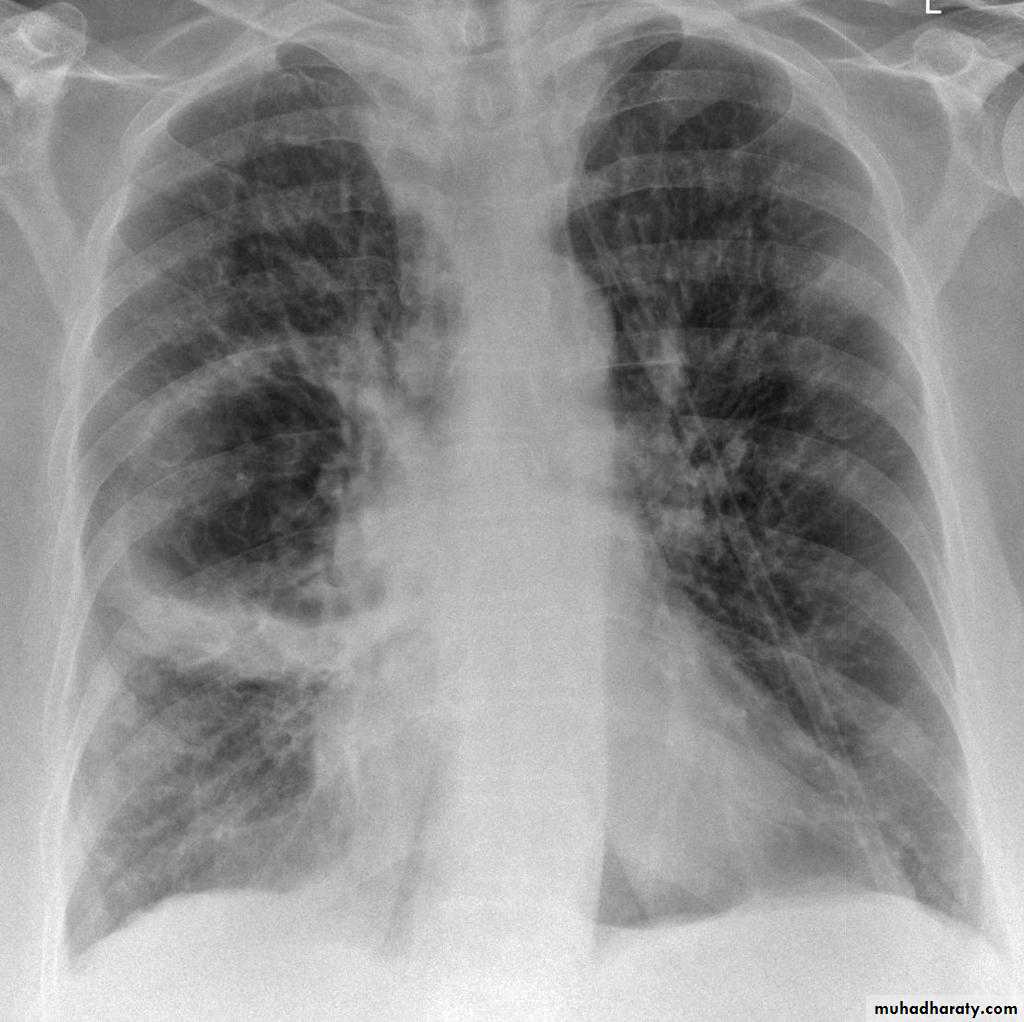

BronchiectasisMany curvilinear opacities in right lung with multiple air fluid levelsHoney comb shadow, Increase in bronchoalveolar markingsPulmonary vasculature appears ill defined